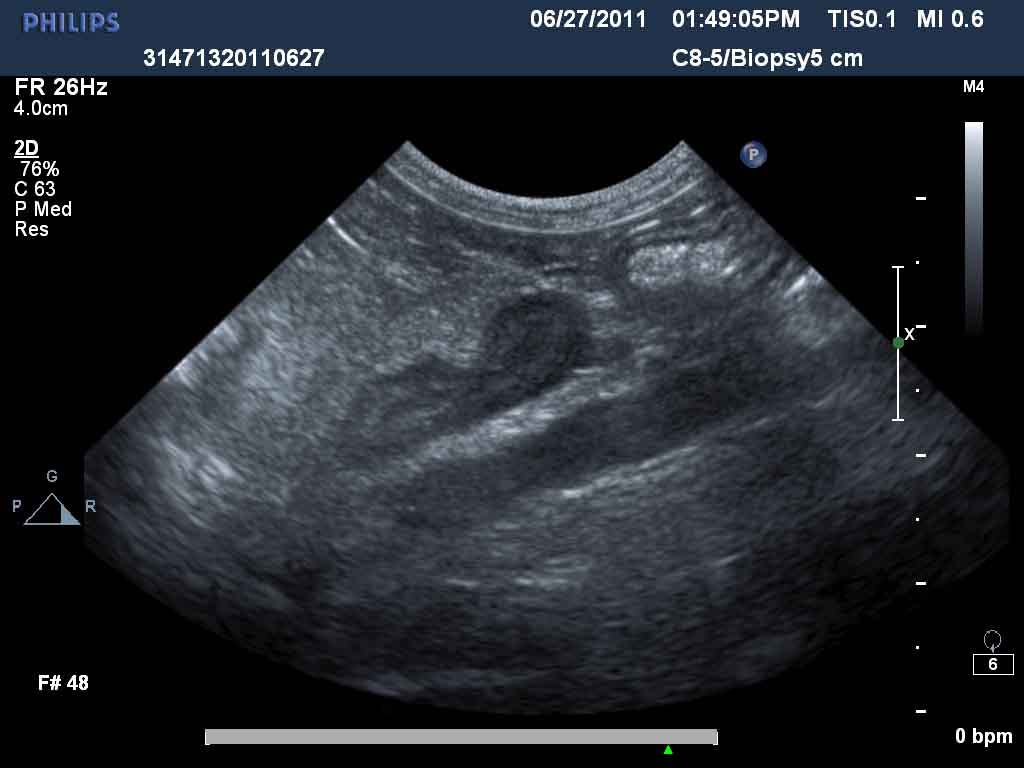

Enlarged Adrenals In Dogs . Bilateral adrenomegaly (>0.8 cm caudal pole widths) has been. Also known as cushing’s disease or. The most common cause (85% to 90% of cases) is a tumor in the. An abdominal ultrasound examination lets your veterinarian see the adrenal glands and determine. Fortunately, with proper treatment, dogs diagnosed with addison’s. Hypoadrenocorticism, more commonly known as addison’s disease, is a disease has serious consequences for dogs. Longitudinal axis view of the left adrenal gland of a dog with a mildly enlarged caudal pole (calipers), measuring 0.84 cm in height. Increased cortisol levels in dogs may result from one of several mechanisms. Named after a neurosurgeon who first described the syndrome in people in 1912. As patients in addisonian crisis are collapsed and hypovolaemic, they require rapid volume expansion, so a fluid bolus is likely to be.

Animal Ultrasound Clinic Enlarged Adrenal in a Pomeranian Enlarged Adrenals In Dogs As patients in addisonian crisis are collapsed and hypovolaemic, they require rapid volume expansion, so a fluid bolus is likely to be. Also known as cushing’s disease or. Hypoadrenocorticism, more commonly known as addison’s disease, is a disease has serious consequences for dogs. Bilateral adrenomegaly (>0.8 cm caudal pole widths) has been. The most common cause (85% to 90% of. Enlarged Adrenals In Dogs.

Adrenal nodules and masses in four dogs Small Animal Ultrasonography Enlarged Adrenals In Dogs Increased cortisol levels in dogs may result from one of several mechanisms. As patients in addisonian crisis are collapsed and hypovolaemic, they require rapid volume expansion, so a fluid bolus is likely to be. Hypoadrenocorticism, more commonly known as addison’s disease, is a disease has serious consequences for dogs. Bilateral adrenomegaly (>0.8 cm caudal pole widths) has been. Named after. Enlarged Adrenals In Dogs.